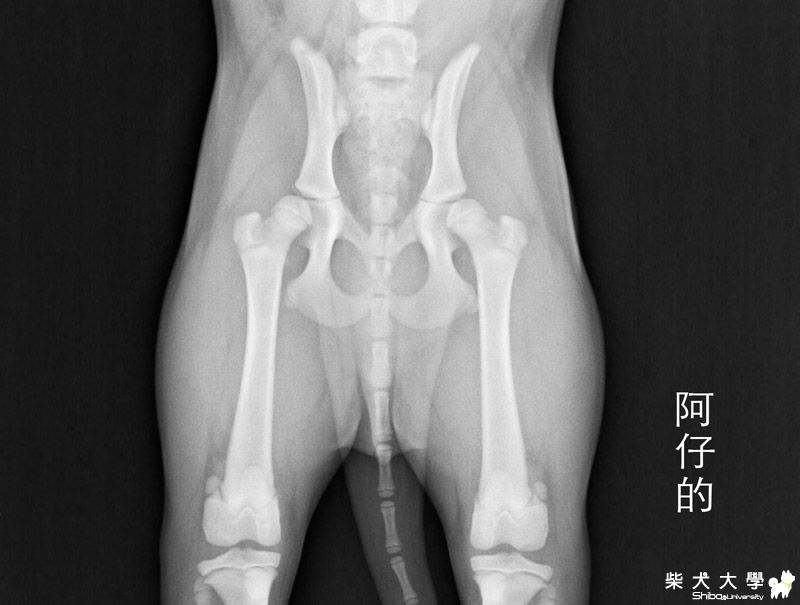

於是,建議拍攝膝及踝的x光片,

拍攝的結果,膝和踝關節都正常,骨頭生長板也都正常,

但髖部的股骨頭和髖臼的密合度不佳,是鬆動的,包覆度不夠,角度也不夠,

但因為髖關節是要兩歲才能做判定的,

現在只能說是髖關節是有鬆動的現象,等六個月大後再追蹤,